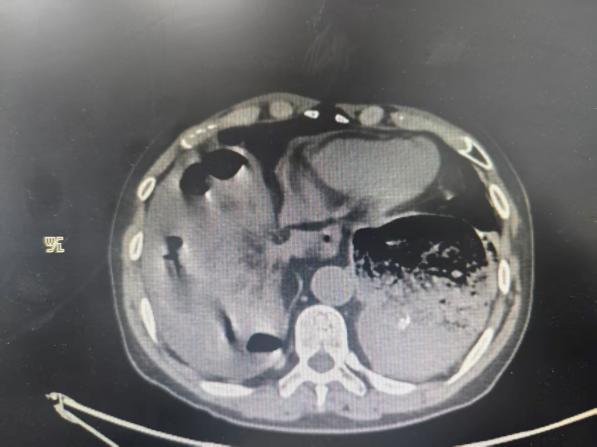

该患者为70岁男性,有8年食管癌手术病史,此次因突发剧烈上腹部疼痛紧急前往我院就诊。急诊快速评估检查后,确诊为膈疝伴嵌顿,病情极危重。检查显示,患者为左胸腔胃,合并右侧纵隔疝,大量肠管疝入胸腔,严重压迫右侧肺组织,导致呼吸困难、生命体征极不稳定,随时可能因肠管坏死穿孔、呼吸循环衰竭危及生命,抢救刻不容缓。

手术中,探查发现患者距回盲部约40cm处回肠经食管裂孔嵌入右侧纵隔并疝入右胸腔,疝入位置深、嵌顿严重,腔镜操作无法完成肠管还纳。专家团队当即紧急研判、优化方案,果断转为开腹探查。胃肠疝外科团队在复杂粘连、严重嵌顿的术野中精细操作,成功将疝入纵隔的肠管完整还纳回腹腔,并确认嵌顿肠管坏死约80cm,随即规范实施小肠切除+肠吻合术,彻底清除坏死病灶、重建肠道通畅。